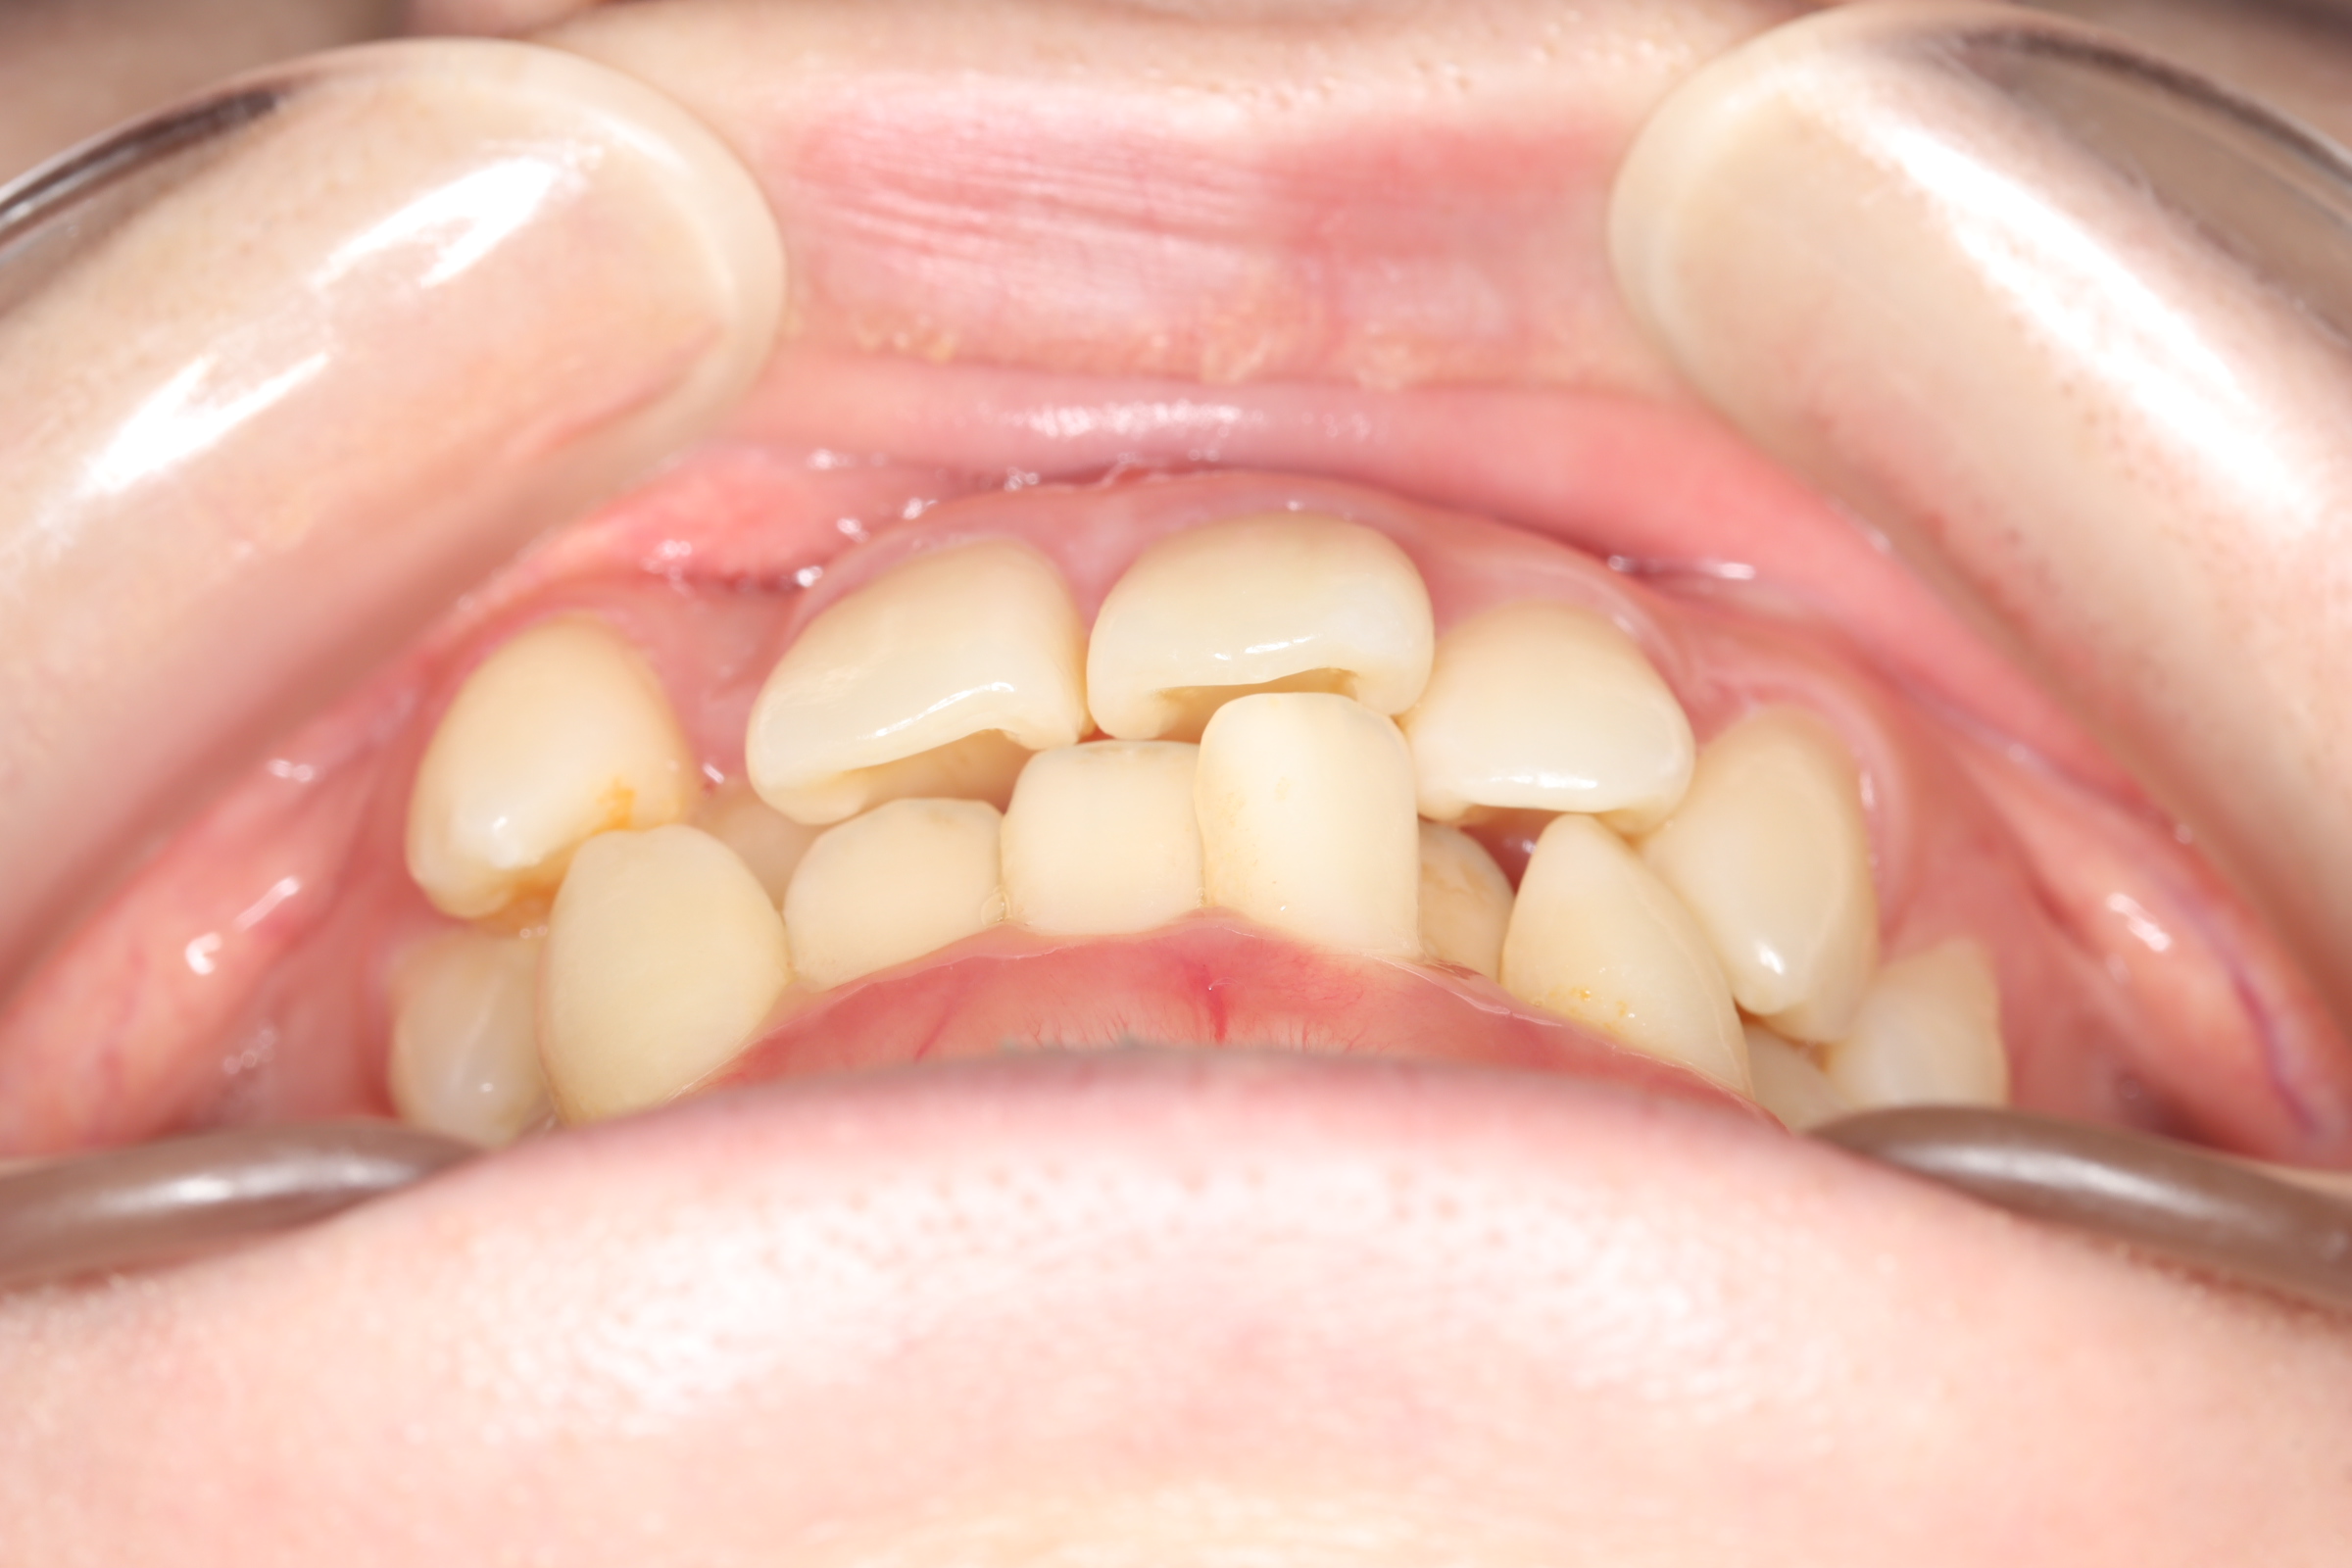

舌側(リンガル)矯正での叢生(ガチャ歯)の治療

口腔内の変化

| 治療前 | SNSなどで「ガチャ歯」と呼ばれている、見た目のがたつきを治したかった患者さんです。 骨格的な問題はありませんでしたが、上下の前歯が唇側傾斜しており、上下顎前突症で口元の突出感がありました。 |